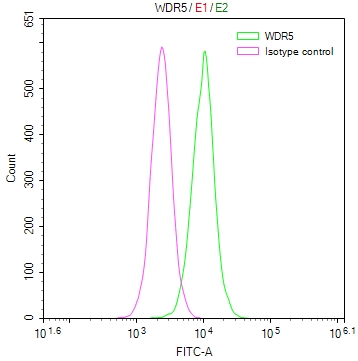

The image on the left is immunohistochemistry of paraffin-embedded Human breast cancer tissue using CSB-PA919263(SPAG4 Antibody) at dilution 1/25, on the right is treated with synthetic peptide. (Original magnification: ×200)

The image on the left is immunohistochemistry of paraffin-embedded Human thyroid cancer tissue using CSB-PA919263(SPAG4 Antibody) at dilution 1/25, on the right is treated with synthetic peptide. (Original magnification: ×200)